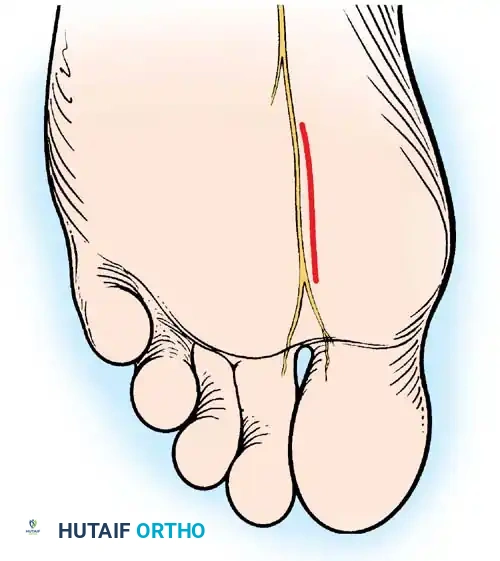

FIBULAR SESAMOIDECTOMY: PLANTAR APPROACH

• If a plantar approach (Fig. 78-21A) is chosen for fi bular sesamoidectomy, have an assistant hold the ankle dorsifl exed, and use a headlight for seeing into the full depth of the wound. Avoid the fl exor hallucis longus tendon and the neurovascular bundle to the fi rst web space.

• Flex and extend the hallux, and inspect the radiograph to locate the sesamoid. Beginning 1 to 1.5 cm distal to the metatarsophalangeal joint, make a longitudinal incision in the plantar surface of the foot, extending the incision proximally 3.5 to 4 cm between the fi rst and second metatarsals.

Fig. 78-21 Fibular sesamoidectomy (plantar approach). A, Incision. B, Common digital nerve to fi rst web space.